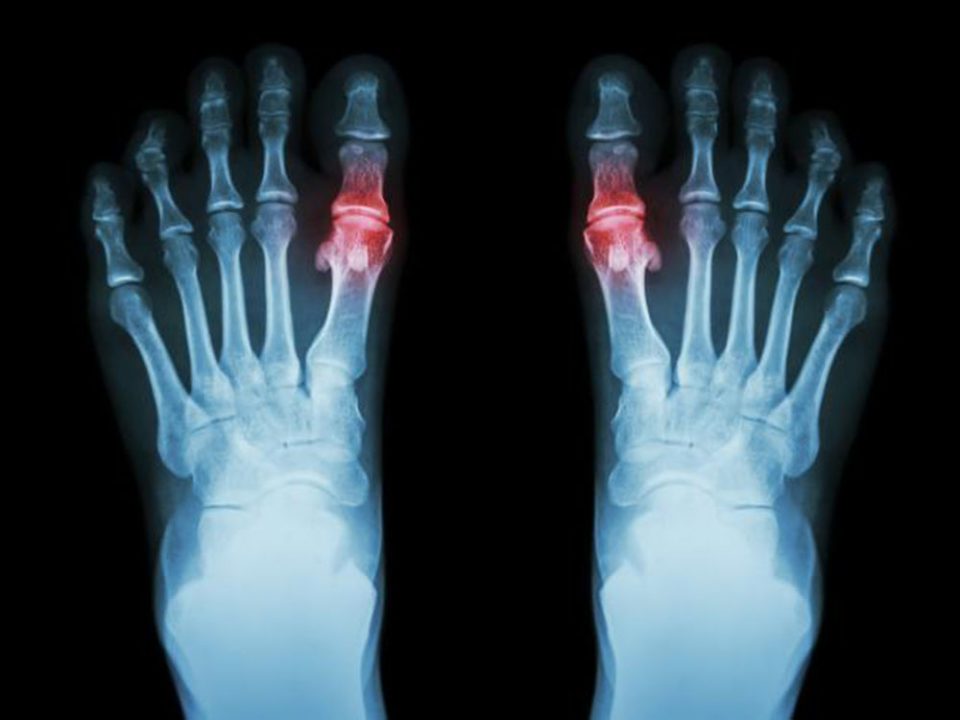

Doença que se caracteriza pelo desgaste da cartilagem articular e por alterações ósseas, entre elas os osteófitos, conhecidos vulgarmente como “bicos de papagaio”